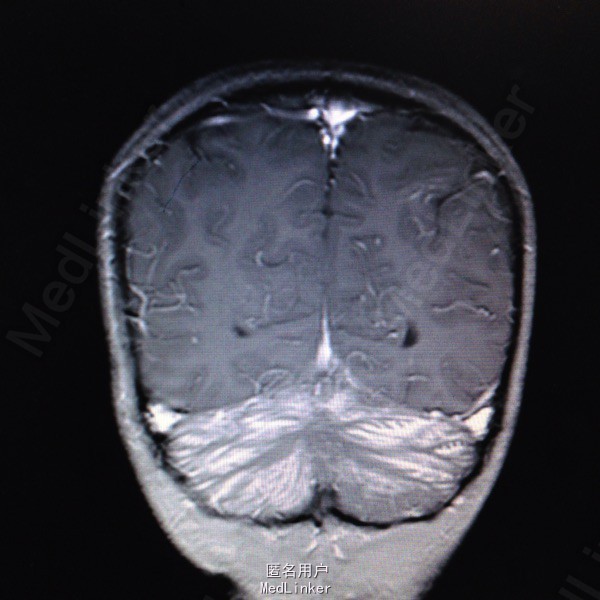

查体:面罩吸氧,甚至浅昏迷,CRT 2s,双侧瞳孔等大等圆,直径约4mm,对光反射迟钝,口唇红润,双肺可闻及干啰音,四肢肌张力偏高,以左侧为主,病理反射Babinski征阳性。辅查:血气分析提示碳氧血红蛋白8.4%,急诊行高压氧治疗,血常规:白细胞14.48G/L,血红蛋白120g/L,血小板291G/L;头颅MR检查:1.双侧小脑半球皮层及皮层下多发脑回样强化,双侧基底节区斑片状强化,结合病史资料,考虑一氧化碳中毒引起;2.双侧乳突炎症。

一氧化碳中毒脑病时多损伤基底节区、额叶、颞叶,本病例除基底节区损伤外,双侧小脑半球皮层及皮层下也受累,临床上还是比较少见的。